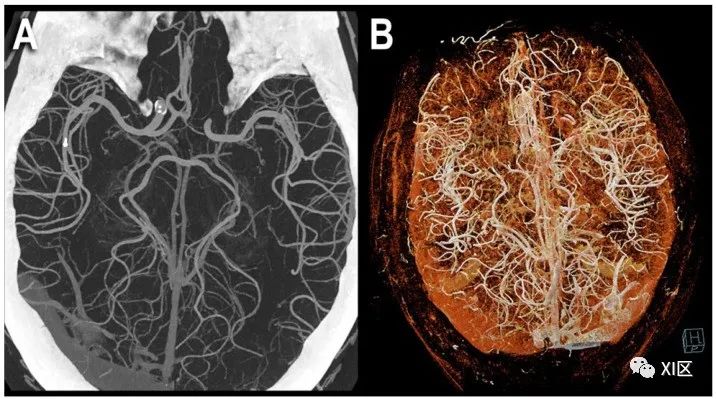

头部PCCT血管造影:三维电影容积渲染显示。图中显示的是100 μm超高分辨率的PCCT脑血管造影(源数据集;矩阵1024×1024;层厚/增量0.2/0.1mm;卷积核Bv60;辐射剂量与使用同类第三代双源CT进行的同等头部CT血管造影相当),使用了容积三维最大密度投影(MIP) (A)和电影容积渲染(B)。值得注意的是,显示的小动脉血管密度大幅增加。

头部PCCT血管造影:MIP容积显示。图中显示的是在三个主要平面:轴向(A)、矢状面(B)和冠状面(C)使用厚片三维最大密度投影(MIP)进行的100 μm超高分辨率PCCT脑血管造影(源数据集;矩阵1024×1024;层厚/增量0.2/0.1mm;卷积核Bv60;辐射剂量与使用同类第三代双源CT进行的等效头部CT血管造影相当)。值得注意的是,所显示的小动脉血管密度和可视段长度大幅增加;(A)为大脑后动脉和中动脉,(B)为大脑前动脉,(C)为大脑中动脉。Symons等人对头颈部主要血管的人体研究比较了PCD技术和EID技术,发现前者在图像噪声(比EID低9.1%)和图像伪影方面表现更好。